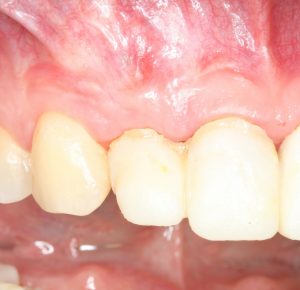

Вот клиническая картина через 4 месяца после ранее проведенной имплантации с остеопластикой:

Как видишь, коллеги из недалекой дружественной страны не осилили снятие швов. Мне это не нравится, хотя и объясняет, почему люди готовы ехать за тыщи километров ради 20-минутной операции удаления зуба мудрости.

Ну хорошо. Швы сняли. Делаем разрез. Обрати внимание, что после всех проведенных операций у нас остается очень небольшой по ширине слой жевательной слизистой оболочки: